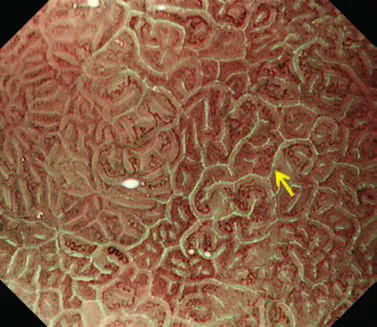

(C) Гастрит, ассоциированный с Helicobacter pylori . Когда слизистая желудка сопровождается Helicobacter pylori-ассоциированный гастрит, микрососудистые и микроповерхностные структуры демонстрируют заметные диффузные изменения по сравнению с нормальной слизистой оболочкой.

А именно, паттерн SECN расширен, и CV не визуализируется в воспаленной слизистой оболочке, в то время как MCE имеет изогнутую / овальную форму, которая отличается от нормальной морфологии, а CO не визуализируется как коричневатая ямка.